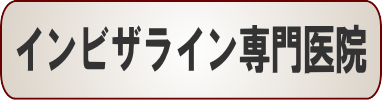

☆歯のデコボコ矯正症例(甲斐様 38歳 女性)